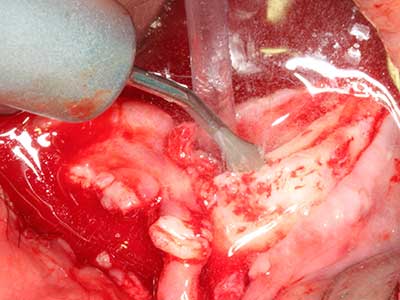

cazione: rialzo del seno

La preparazione della finestra laterale durante un rialzo del pavimento sinusale esterno è complicata, in particolare per gli implantologi con poca esperienza chirurgica. La rimozione della copertura ossea del seno senza danneggiare la membrana schneideriana sottostante è solo una parte dell'operazione: dopo aver stabilito un accesso adeguato, la membrana interna del seno deve essere spostata con cautela per far spazio ai materiali di accrescimento o agli impianti. La piezochirurgia è utile per questa indicazione in due modi: è possibile utilizzare gli strumenti diamantati per l'ablazione selettiva dell'osso e, se la procedura viene eseguita con precisione, la membrana mucosa sottostante rimane intatta. Le frequenze ultrasoniche permettono anche la separazione della membrana mucosa senza complicanze: le frequenze vengono trasmesse nello spazio compreso tra la membrana mucosa e il pavimento sinusale mediante degli speciali raccordi smussati (Cassetta, Ricci et al. 2012, Pereira, Gealh et al. 2014) (Rickert, Vissink et al. 2013). Di conseguenza, non sorprende che le rivisitazioni attuali del rialzo del pavimento sinusale esterno valutino positivamente l'utilizzo dei dispositivi piezoelettrici, delle superfici non lisce degli impianti e dei materiali di riempimento dell'osso (Wallace, Tarnow et al. 2012).